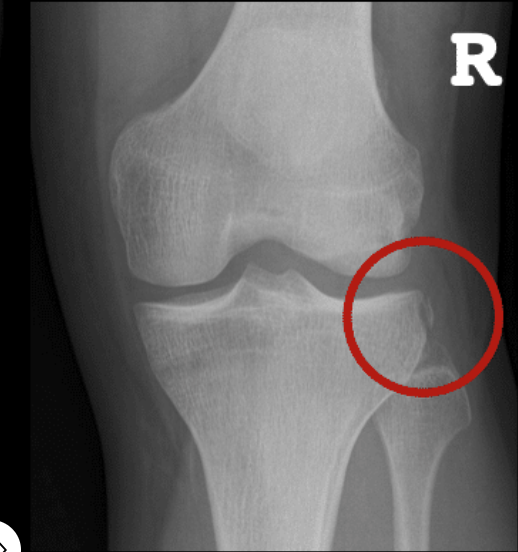

Segond #

A

A Segond fracture = ACL tear

Avulsion fracture on the lateral tibial condyle at the site of attachment of the lateral capsular ligament